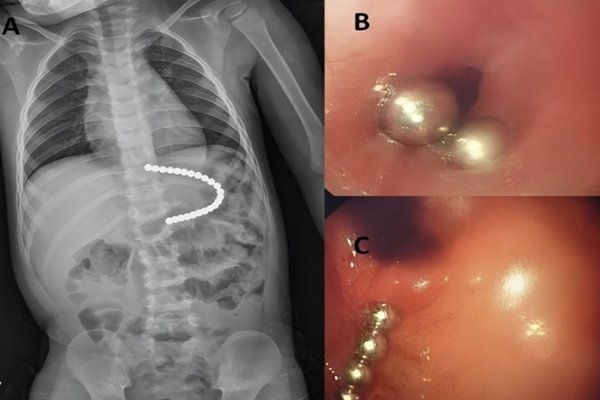

Diagnostic Imaging: The X-ray

Â

The single most important diagnostic tool is an X-ray. It is non-invasive and provides a clear picture of what is happening inside the body.

The X-ray will confirm several crucial facts:

- Confirmation: Are there actually magnets inside?

- Quantity: How many magnets are present? An X-ray will clearly show if there is one or more.

- Location: Where are the magnets in the digestive tract? Are they in the stomach, the small intestine, or the colon?

- Configuration: Are the magnets separated, or have they already attracted each other and trapped tissue? They may appear as a single object on the X-ray if they are already stuck together.Â

Doctors may take a series of X-rays over a few hours. This shows if a single magnet is moving through the system. It also shows if multiple magnets are staying in one place, which is a sign they are attached across bowel walls.